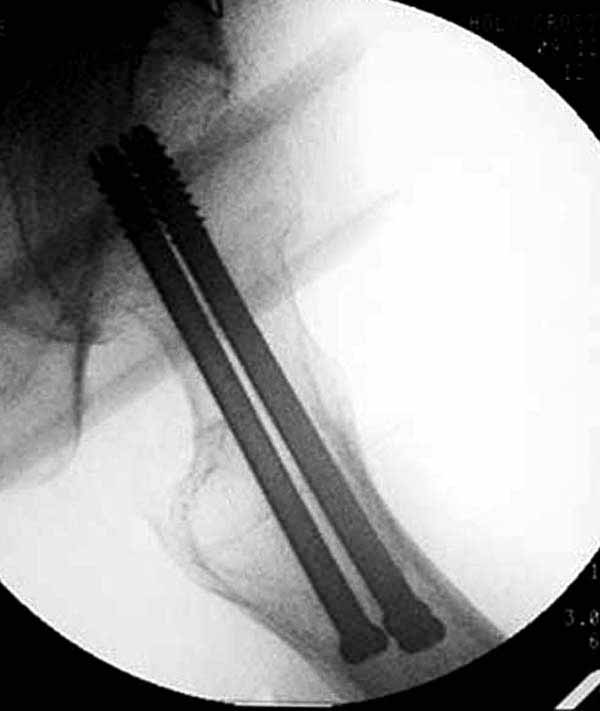

Пациентка Ш. 76 лет, 11 дней назад прооперирована по поводу вколоченного субкапитального перелома шейки левой бедренной кости, 3-мя канюлированными винтами. Вчера пациентка упала в палате. И вот результат- подимплантатный подвертельный перелом левой бедренной кости. Уважаемые коллеги, пожалуйста посоветуйте какой метод дальнейшего лечения предпринять дальше.Соматически пациента повышенного питания, страдает варикозной болезнью нижних конечностей.Из предложенных вариантов коллег - целллокастовая укороченная кокситная повязка, скелетное вытяжение сроком на 40-45 суток - отпали сразу, так как необходимо активизация пациентки.На данный момент рассматриваем следующие варианта реостеосинтеза:(наличие технических возможностей) 1. Длинная Gamma 3 Stryker (с предварительной интраоперационной фиксацией головки спицами).2. Трохантерный штифт DePuy с 2-мя метафизарными винтами в проксимальном отделе, (также с интраоперационной фиксацией головки спицами. Очень настораживает стабильность фиксации с проксимальном отделе с связи с выборкой костной ткани ранее находящимися там канюлированными винтами. Сейчас пациентка находится на скелетном вытяжении, с дисциплинирующим грузом. Операция планируется после праздников. Заранее извиняемся за качество и неполное соответствие проекций на R-ммах (R-служба отдельная песня). При интраоперационном ЭОП-контроле винты в аксиальной проекции разнесены по шейке.

два в нижней части шейки. Более стабильная структура как раз обратная: два шурупа в проксимальной части шейки , и не дальше центральной части головки, иначе есть риск пенетрации. дистальный винт мог бы быть выше уровня малого вертела. Его дистальное расположение описано с увеличенным риском послеоперационного перелома.

Как отметили коллеги, необходимо обратить внимание на последовательность введения каннюлированных шурупов. Рекомендуется введение в форме “V”, т.е основанием вниз, потому что в другой последовательности за счет увеличения стресса латерального кортекса имеется риск перелома. За редким исключением удается установить Guide wire с первой попытки и многоразовые пробы спицей увеличивают стресс. Небольшая травма может привести к перелому.